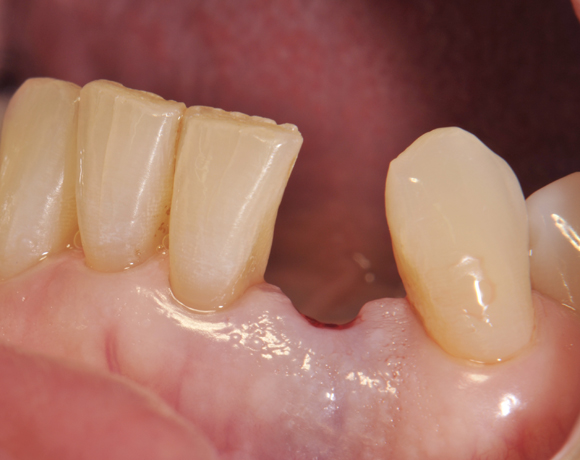

Am Beispiel dieses Patientenfalls wird gezeigt wie ein Einzelimplantat für den Unterkieferfrontzahn 33 eingesetzt wird.